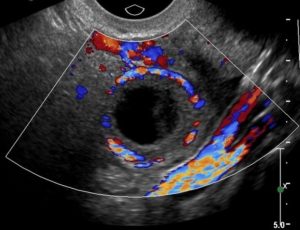

Самой частой физиологической причиной увеличения детородного органа и появления в нем темного пятна становится зачатие. Анэхогенное включение в матке, расположенное на стенке, говорит о том, что это плодное яйцо.

Во время исследования сонолог обнаруживает круглое или овальное включение с ровными краями и однородной структурой, имеющее небольшой размер. Примерно до 6 акушерских недель беременности увидеть эмбрион не удается, поэтому в протоколе УЗИ указывается только наличие анэхогенного включения.

По дополнительным симптомам врач с большой вероятностью устанавливает причину присутствия темного включения (в яичнике желтое тело, эндометрий пышный, есть задержка менструации). После 6-7 недель картина ультразвука меняется.

Анэхогенное включение по-прежнему присутствует, но в своей полости оно уже содержит эмбрион, у которого отчетливо видно сердцебиение. При таких результатах сомнений не остается.

- До шестой недели вынашивания ребенка его обнаруживают вверху матки. Это плодное яйцо. При выполнении УЗИ на краях образования виден гиперэхогенный ободок.

В процессе проведения УЗИ желтое тело тоже определяется как черное пятно. Таким образом, при выявлении образований в матке паниковать не следует. Темное пятно может свидетельствовать о развитии нормальной беременности, указывать на желтое тело или появление кисты, которая исчезнет без усиленного лечения.